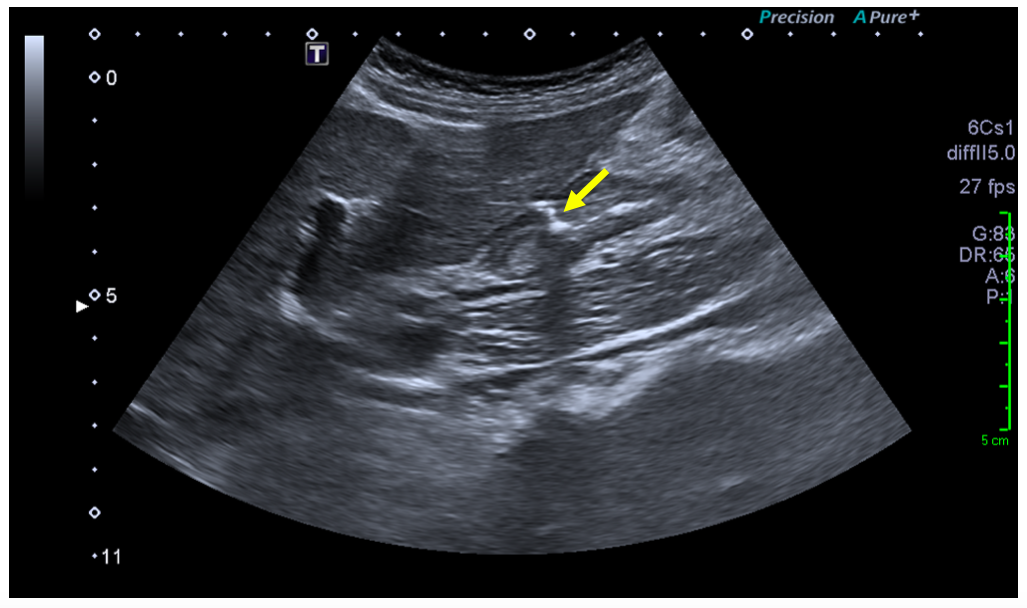

Sonographic examination demonstrated a full thickness mucosal defect of the anterior pre-pyloric region of the stomach, with extraluminal gas locules (see image), trace free fluid in the gallbladder fossa and complex fluid in the right iliac fossa. These features were consistent with a perforated pre-pyloric gastric ulcer. An urgent CT scan was arranged, which confirmed the diagnosis (see images). The patient subsequently underwent emergency laparoscopic surgery. The perforated ulcer, loosely sealed by omentum and the medial edge of the liver, was identified and repaired with an omental plug procedure. Further management included postoperative intravenous antibiotics and PPIs. The patient made a good recovery and was discharged four days post-operatively, with Helicobacter pylori eradication therapy and analgesia.

An active peptic ulcer may be visualised as a localised, asymmetric thickening of the gastric or duodenal wall, with or without echogenic gas in the ulcer crater. A perforated peptic ulcer may be seen directly as a whole-thickness defect, with an echogenic linear track of gas locules originating from the ulcer crater and extending extraluminally into the peritoneal cavity [2, 8].

Indirect signs include localised extraluminal gas, pneumoperitoneum, fluid collections and inflammatory fatty change. Extraluminal gas locules accumulate close to the site of perforation, and may be evident even in small volumes; visualisation should promote further focused examination of the region. Pneumoperitoneum may be significant, with free intraperitoneal air collecting in the perigastric, periduodenal and/or perihepatic spaces. Free fluid may be present in variable volume; in some cases limited locally to the perforation site, and in others present in larger volume, extending to the perihepatic space, along the right paracolic gutter and into the pelvis. Fatty inflammatory change local to an active ulcer may also provide subtle indirect evidence of peptic perforation [8].